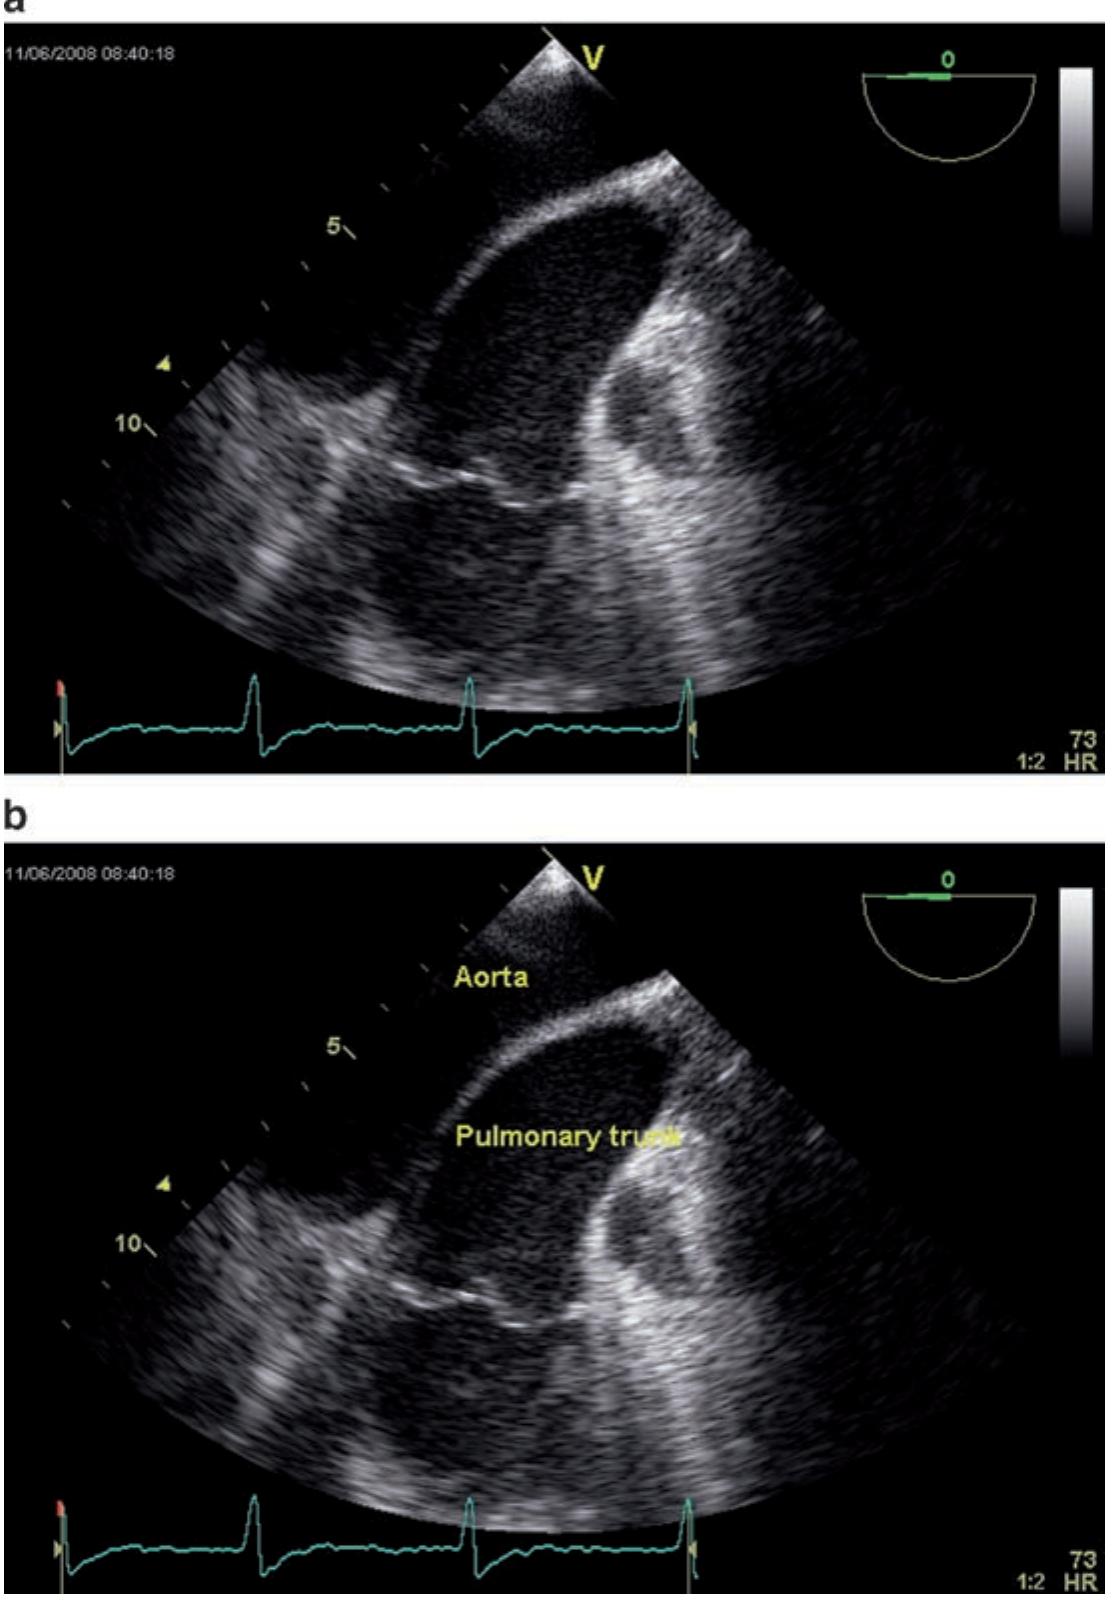

健康+医学 Transesophageal Echocardiography Transesophageal Echocardiography (TEE) | Heartplaceの詳細情報

Transesophageal Echocardiography (TEE) | Heartplace。PDF) Transesophageal Echocardiography in Clinical Practice。Transesophageal Echocardiography | Circulation。

Transoesophageal Echocardiogram - YouTube

題名:PracticalApproachtoTransesophagealEchocardiography,4thed.

著者:A.C.PerrinoJr.&S.T.Reeves(eds.)

出版社:WOLTERSKLUWER

ISBN:978-1-4963-8347-1

ページ数:643pp.

出版年:2020年

定価24,739円(本体22,490円+税)

題名:PracticalApproachtoTransesophagealEchocardiography,4thed.

著者:A.C.PerrinoJr.&S.T.Reeves(eds.)

出版社:WOLTERSKLUWER

ISBN:978-1-4963-8347-1

ページ数:643pp.

出版年:2020年

定価24,739円(本体22,490円+税)